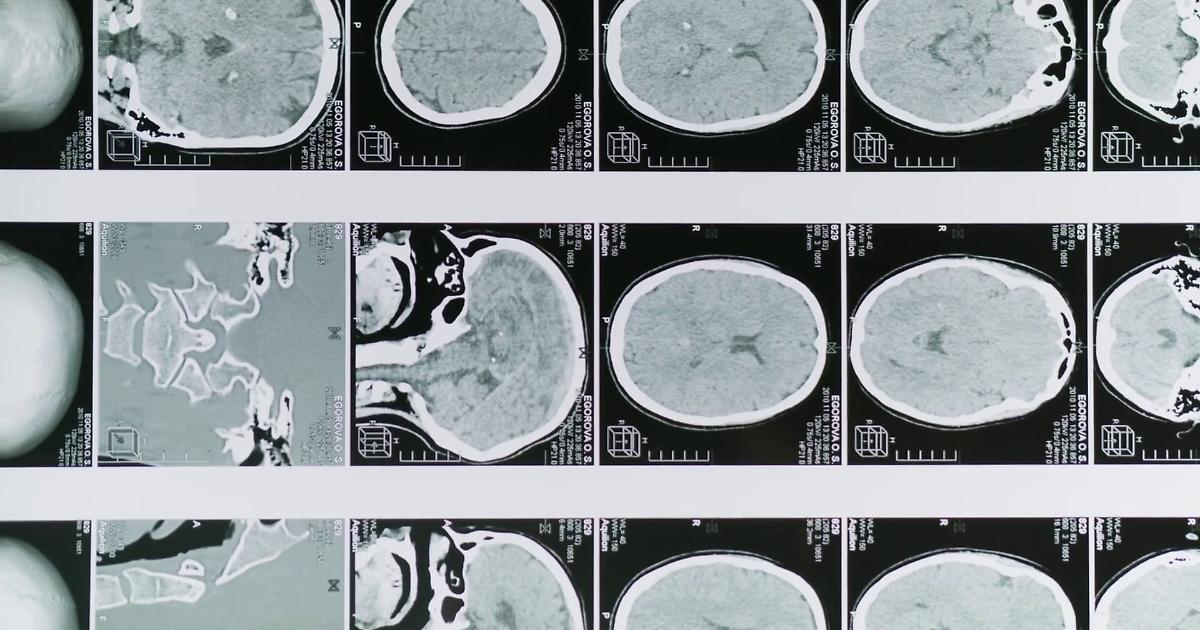

Glioblastoma, le molecole naturali migliorano la chemioterapia